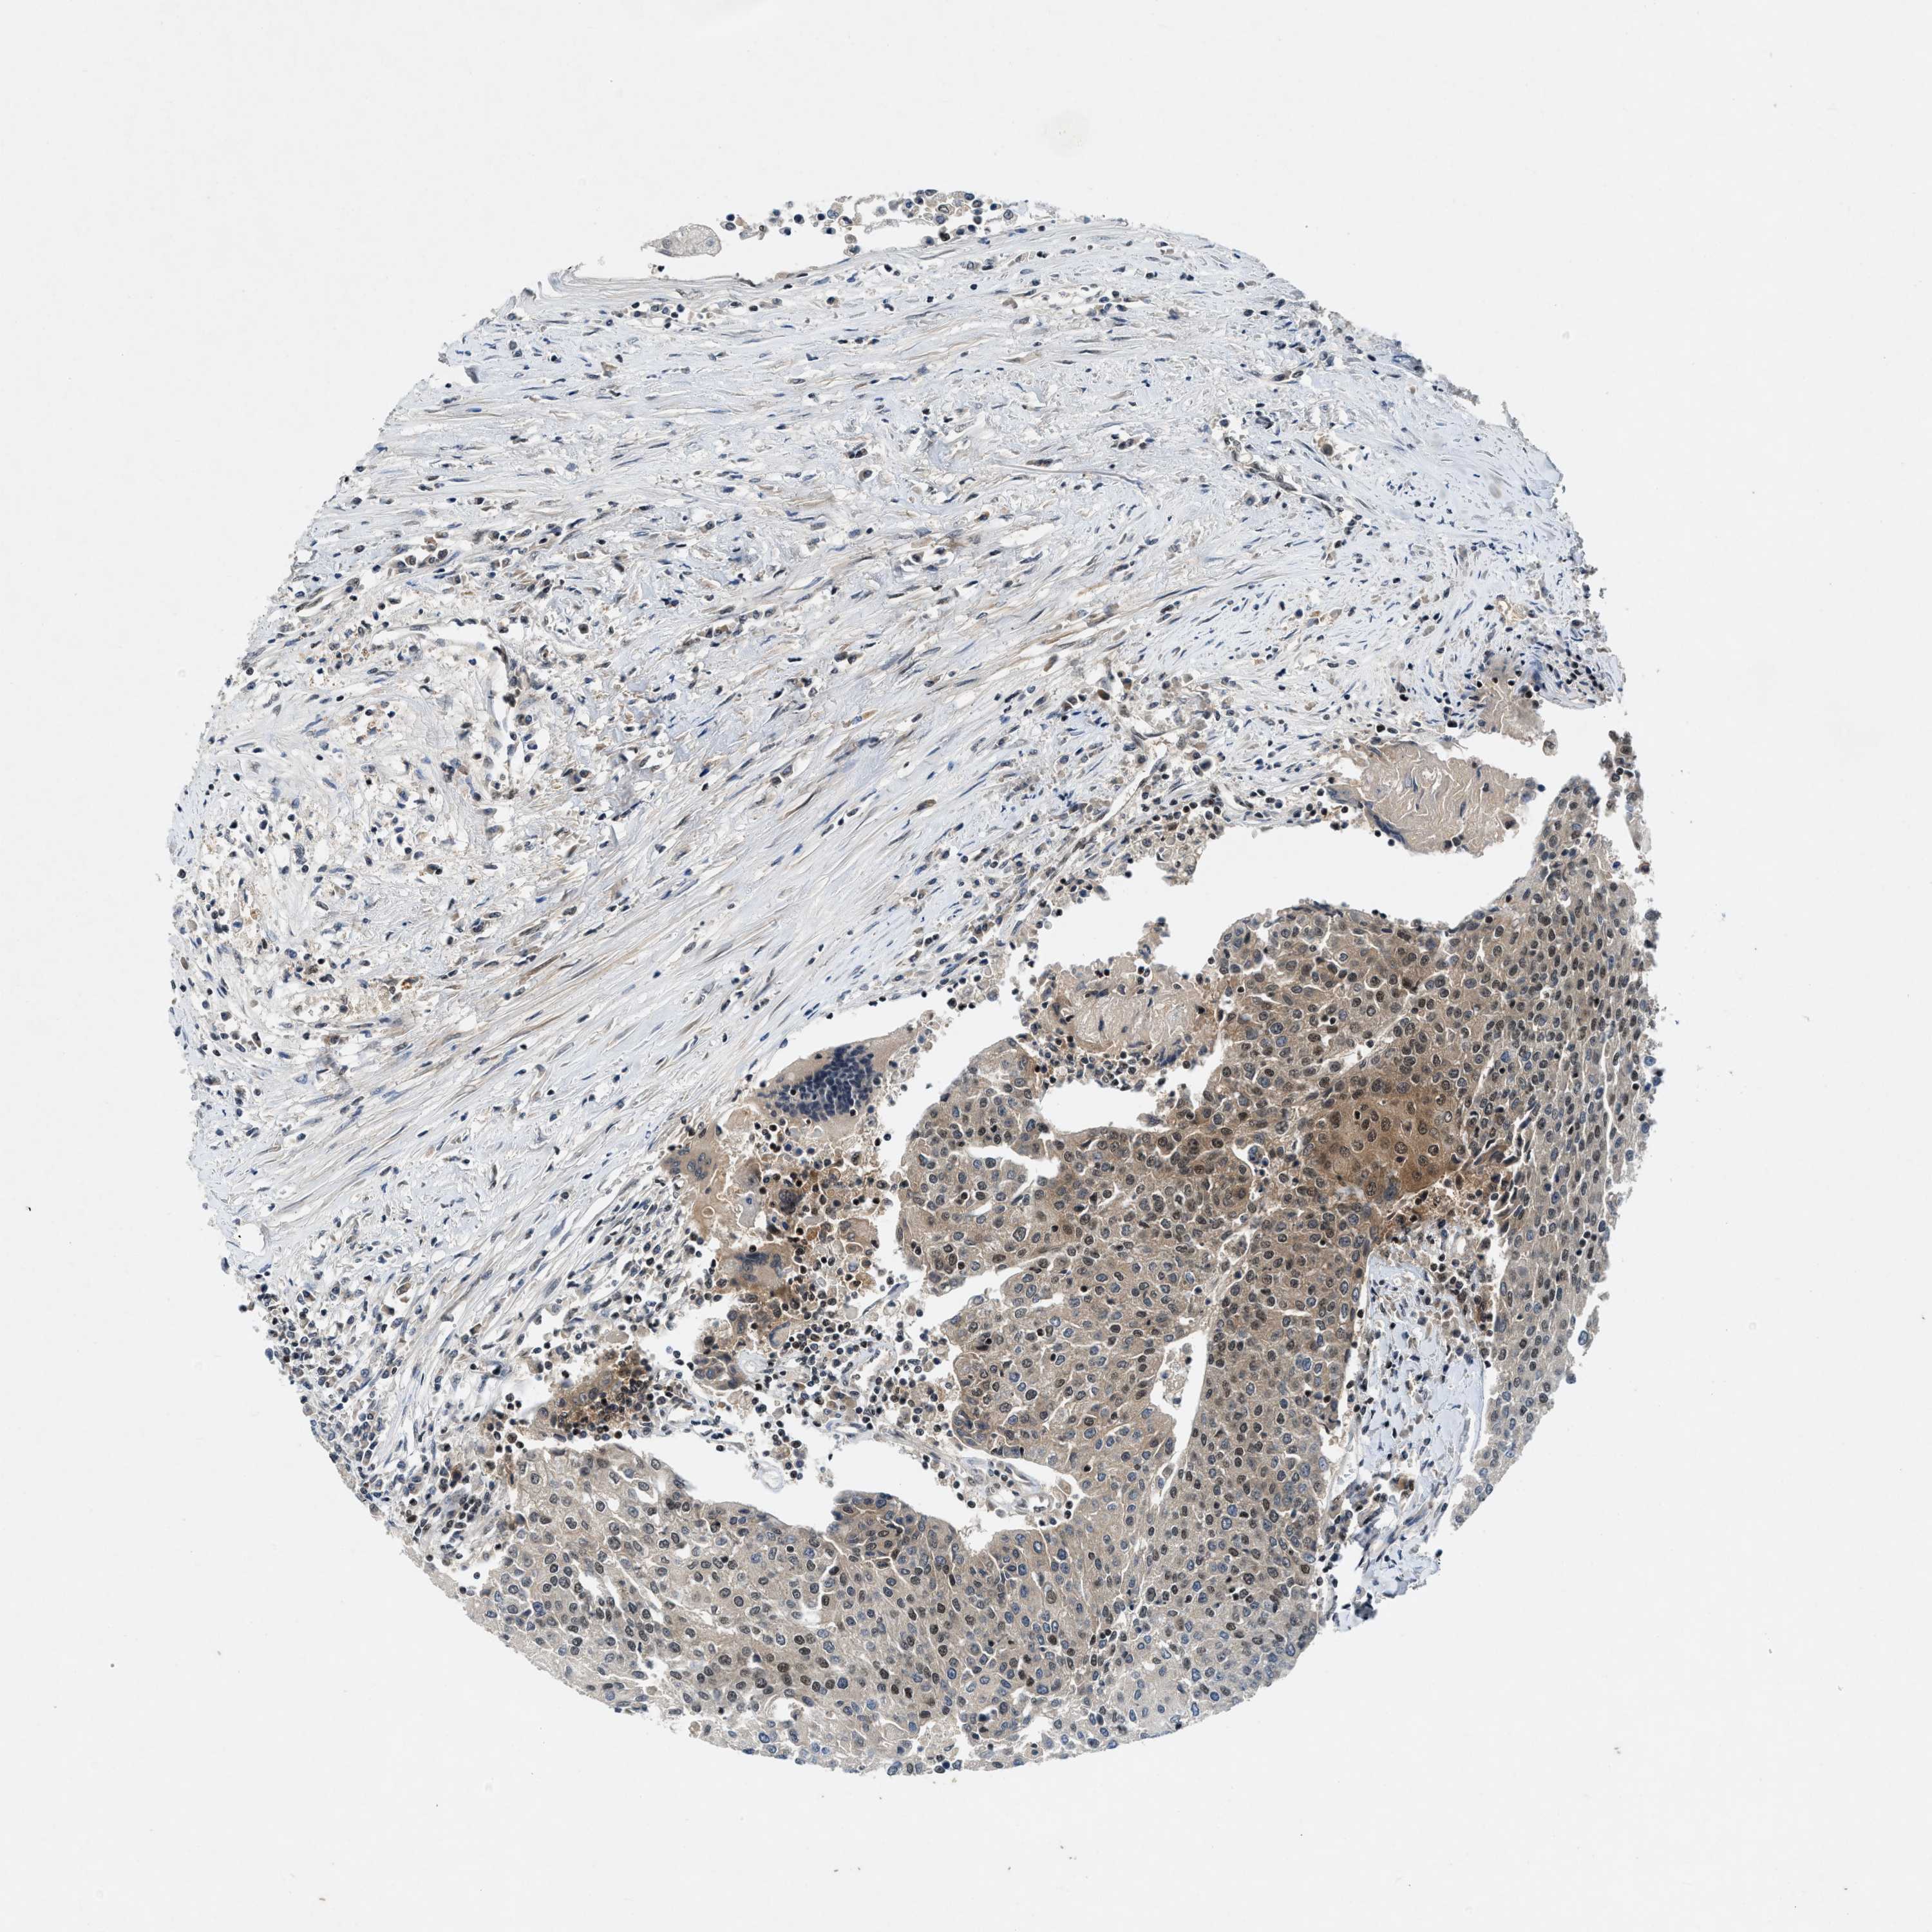

UROTHELIAL CANCER - Protein expressioni

A mouse-over function shows sample information and annotation data. Click on an image to view it in a full screen mode. Samples can be filtered based on level of antibody staining by selecting one or several of the following categories: high, medium, low and not detected. The assay and annotation is described here.

Antibody stainingi

Antibody staining in the annotated cell types in the current human tissue is reported as not detected, low, medium, or high, based on conventional immunohistochemistry profiling in selected tissues. This score is based on the combination of the staining intensity and fraction of stained cells.

Each image is clickable and will lead to virtual microscopy that enables deeper exploration of all samples and also displays staining intensity scores, fraction scores and subcellular localization as well as patient and tissue information for each sample.

Antibody CAB019402

Staining

High

Medium

Low

Not detected

Intensity

Strong

Moderate

Weak

Negative

Quantity

>75%

75%-25%

<25%

None

Location

Nuclear

Cytoplasmic/membranous

Cytoplasmic/membranous,nuclear

Urothelial carcinoma, Low grade

Urothelial carcinoma, High grade